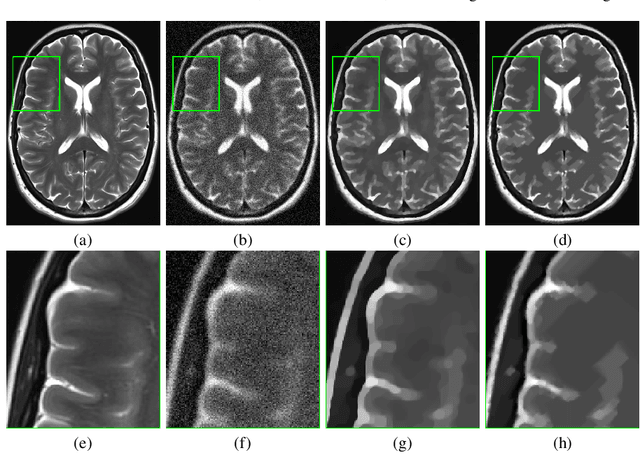

Abstract:In this paper we present a new regularization term for variational image restoration which can be regarded as a space-variant anisotropic extension of the classical isotropic Total Variation (TV) regularizer. The proposed regularizer comes from the statistical assumption that the gradients of the target image distribute locally according to space-variant bivariate Laplacian distributions. The highly flexible variational structure of the corresponding regularizer encodes several free parameters which hold the potential for faithfully modelling the local geometry in the image and describing local orientation preferences. For an automatic estimation of such parameters, we design a robust maximum likelihood approach and report results on its reliability on synthetic data and natural images. A minimization algorithm based on the Alternating Direction Method of Multipliers (ADMM) is presented for the efficient numerical solution of the proposed variational model. Some experimental results are reported which demonstrate the high-quality of restorations achievable by the proposed model, in particular with respect to classical Total Variation regularization.